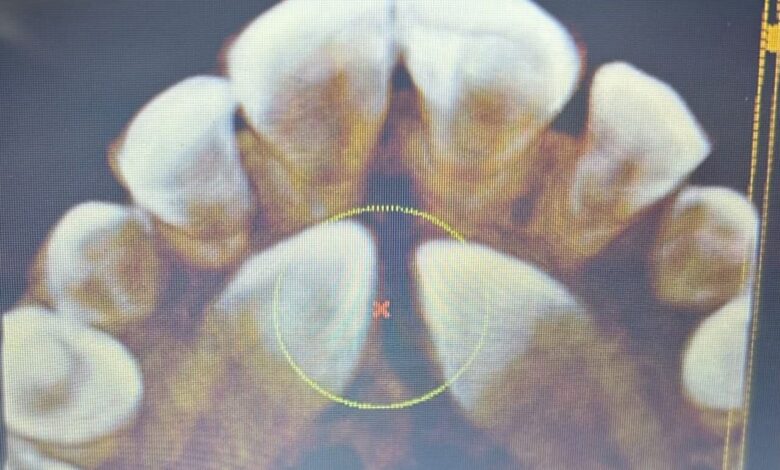

اجريت في وحدة جراحة الفم التابعة للمركز التخصصي لطب الاسنان الاول عملية جراحية لمراجعة بعمر ٢١ عاماً تعاني من انياب مطمورة في الفك العلوي .

واوضح طبيب الاسنان المعالج الدكتور علي عقيل القريشي اجراء عملية جراحية تم خلالها قلع الانياب المطمورة في الفك العلوي وازالتها بشكل كامل ، لتكمل بعدها مراحل عملية تقويم الاسنان لاستعادة انتظامها وتحسين مظهر الابتسامة .